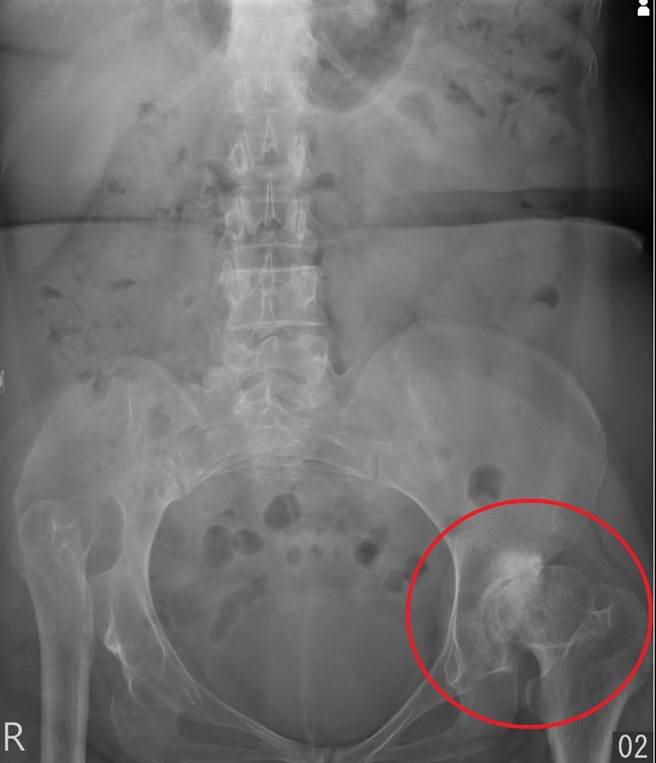

林女士双侧都患有髋关节发育不良,左侧的髋关节软骨严重磨损,关节间隙几乎完全丧失。(长安医院提供/冯惠宜台中传真)

走路下背痛,未必是脊椎退化狭窄,也可能是髋关节退化所致。一名60岁林女士因下背痛及左臀疼痛导致举步维艰,起初被骨科诊所诊断为是脊椎退化狭窄造成,唯復健一年仍无改善,最后到长安医院骨科求治,透过详细的理学检查及影像学检查,才左侧髋关节发育不良导致次发性髋关节退化,经进行人工髋关节置换术后隔天,林女士已可下床走路。

林女士到院后,赵子镕经细心问诊,并进行详尽的理学检查,最终发现她患有严重的髋关节发育不良,进而导致次发性髋关节退化。他解释,这个诊断结果显示真正的病根不在脊椎,而是左侧髋关节软骨完全磨损所导致的疼痛,让她的步伐变得十分艰难、走路就痛,困扰林女士长达一年多的下背痛的病根终于水落石出。